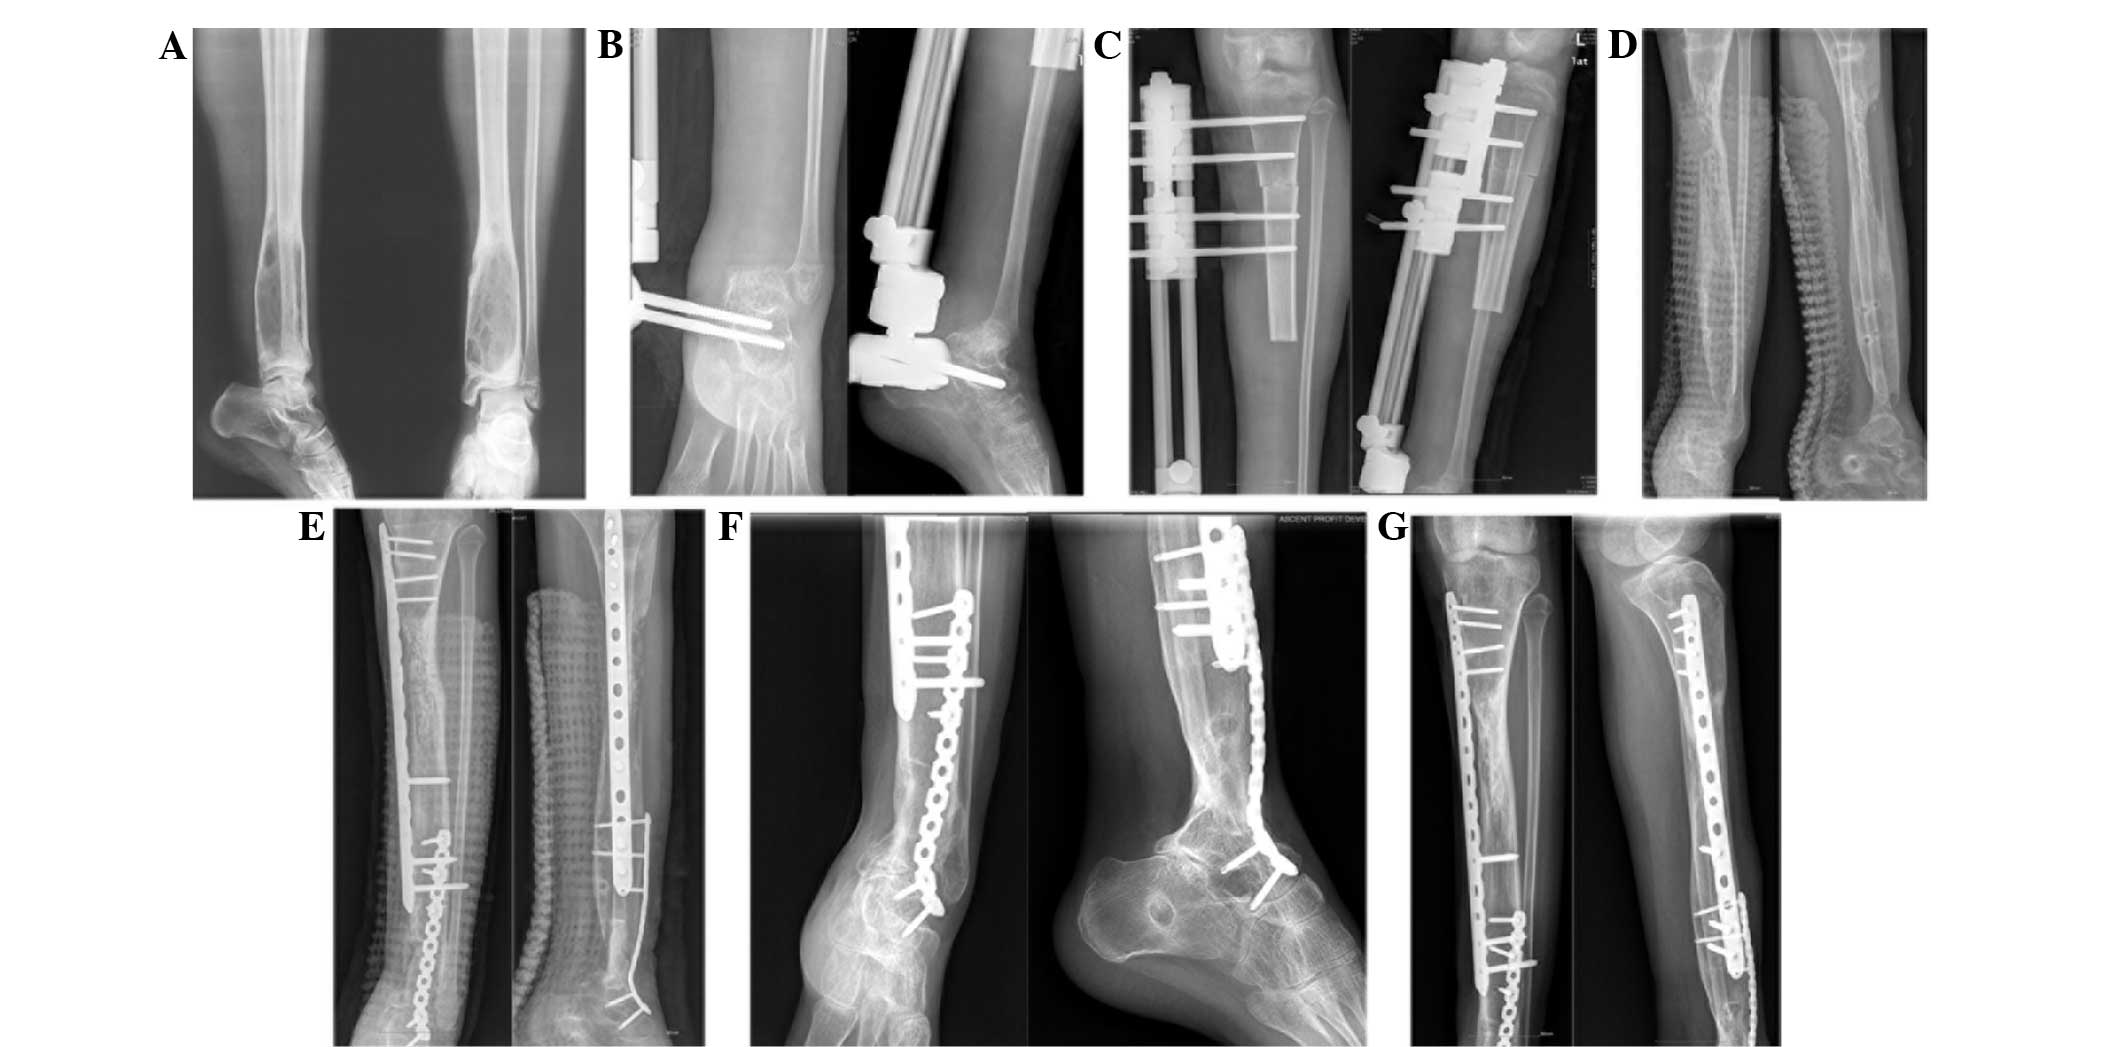

Figure 1.

Case 1. Osteosarcoma in the proximal tibial region of a 29-year-old man. (A) Preoperative radiograph showing the lesion. (B) Following resection of the tumor, the tibia was fixed using an Orthofix external fixator. (C) Autologous bone grafts were harvested from the ilium and implanted into the callus 16 months subsequent to initiation of bone transport distraction. (D) Bone union was observed 3 months following bone grafting. (E) Radiograph showing bone consolidation following the removal of the fixator.

Figure 2.

Case 2. Osteosarcoma of the distal tibial region in a 16-year-old girl. (A) Preoperative radiograph showing osteolysis in the distal tibial region. (B and C) The tibial bone defect was fixed using an Orthofix external fixator. (D) Bone consolidation subsequent to 28 months of distraction osteogenesis. (E) Fusion of the ankle joint, following autologous grafts from the ilium being implanted into the ankle joint and the callus. An internal fixator was also implanted. (F and G) Bone union 3 months following bone grafting.